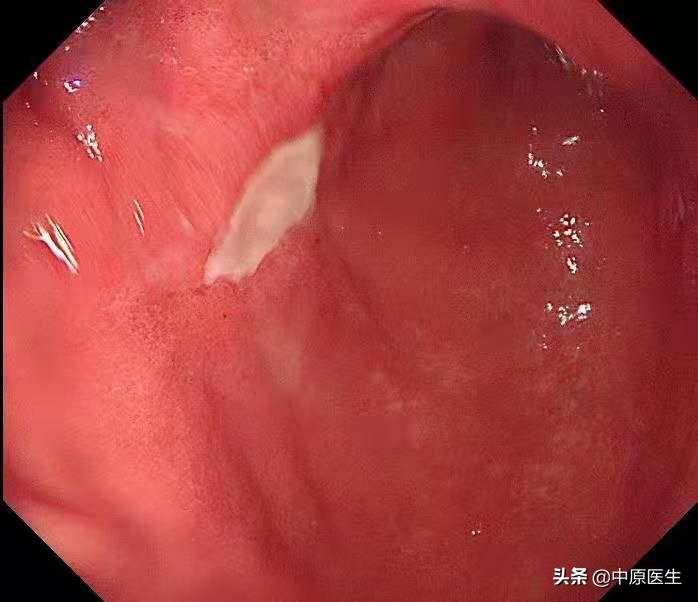

我接着按照程序仔细检查每一个角落,结果在胃角的前壁、胃窦后壁又分别发现了一个溃疡,

通常,在胃镜检查时发现溃疡病变,需要做良恶性鉴别,内镜下鉴别良性和恶性溃疡(也就是通常说的胃癌)需要从以下几个方面考虑,第一、病变的大小,大的溃疡恶性的可能性大。第二、形状,恶性溃疡往往形状不规则;第三、恶性溃疡的底部往往凹凸不平;第四、恶性溃疡表面的苔往往污秽(很脏);第五、恶性溃疡的边缘多伴有结节样隆起,反之,则良性可能大。

这个患者的溃疡多发,不算太大,并且表面的苔很干净,底部也算平坦,尤其是新发现的两个溃疡,从这几个条件来看,似乎良性可能性大。但是,我还是不放心。我现在只是用了白光检查,为什么不选择窄带光,放大检查?虽然麻烦一点,但是,可以看到更多细节!于是,我打开NBI模式,并且使用变焦(俗称放大,可以达到和显微镜下看类似的效果),再仔细地对每一处病变进行了观察,结果竟然发现,虽然范围很小,尤其是胃窦处的溃疡,不超过2个毫米的范围内我都发现了腺管缺失和血管异常扩张的地方,这往往提示病变有可能已经癌变,在放大镜的引导下,我对病变进行了精准活检。